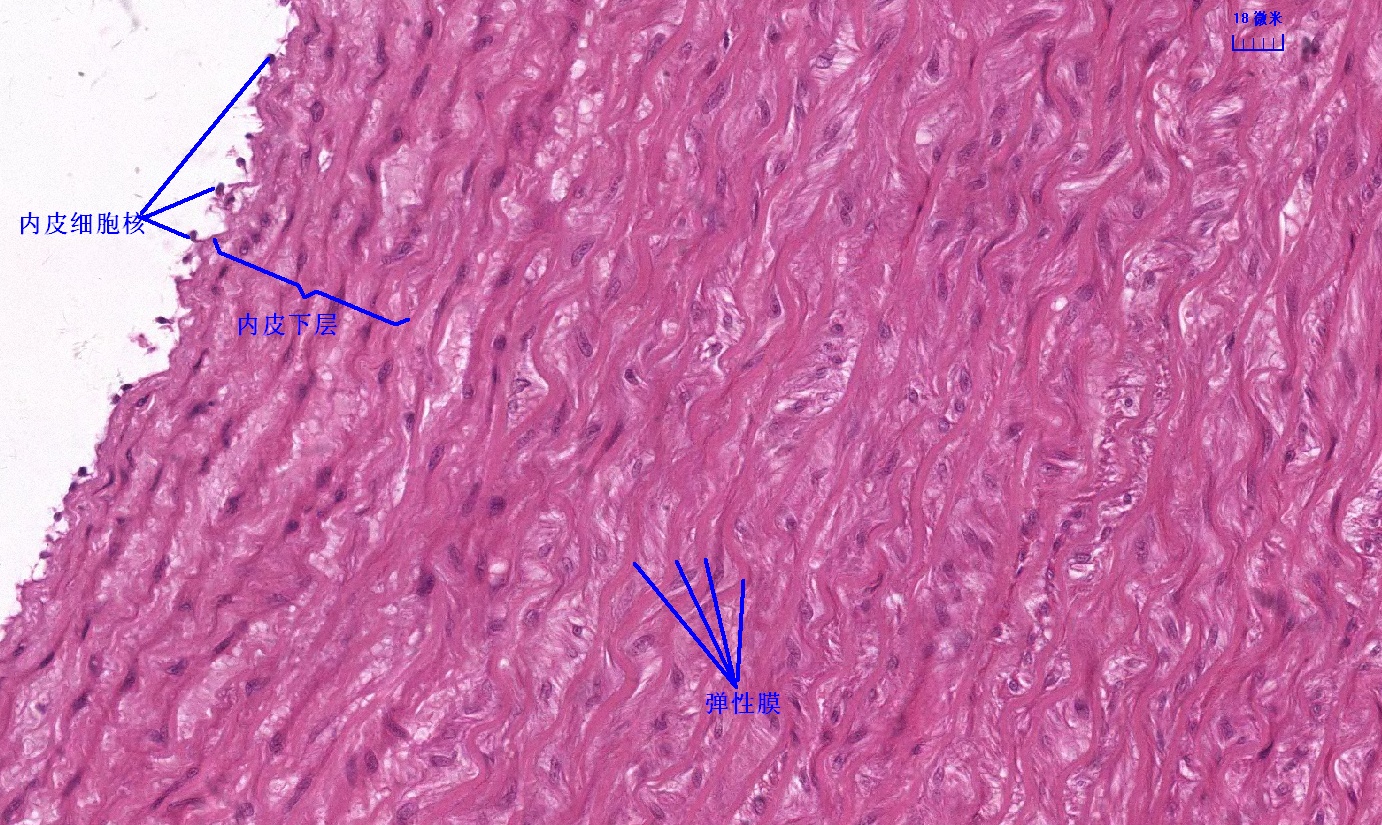

6 第六单元 循环系统

6.1 循环系统切片库

6.2 循环系统微课

6.3 循环系统课件